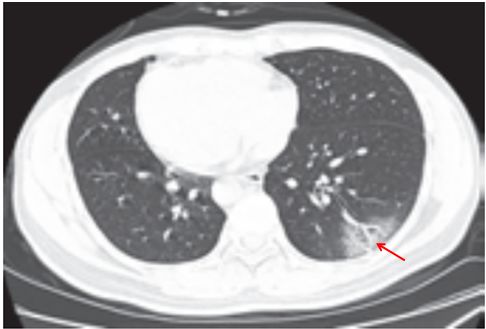

与肺部支原体感染的鉴别诊断

支原体肺炎是由支原体引起的以间质性改变为主的肺炎。支原体侵入肺内可引起支气管、细支气管黏膜及周围间质充血和水肿,多核细胞浸润,侵入肺泡可产生肺泡浆液性渗出炎症。病变范围可从小叶、肺段至大叶。多数患者症征不符:临床症状重,影像学表现较轻。

实验室检查支原体抗体呈阳性,发病 2~3 周后血冷凝集试验比值升高(可达 1∶64)。

影像学表现:

(1) HRCT 显示更清晰,呈树雾征(图 3-13A)、树芽征(图 3-13B),可出现支气管壁增厚。

(2)渗出实变较淡,常合并支气管肺炎。